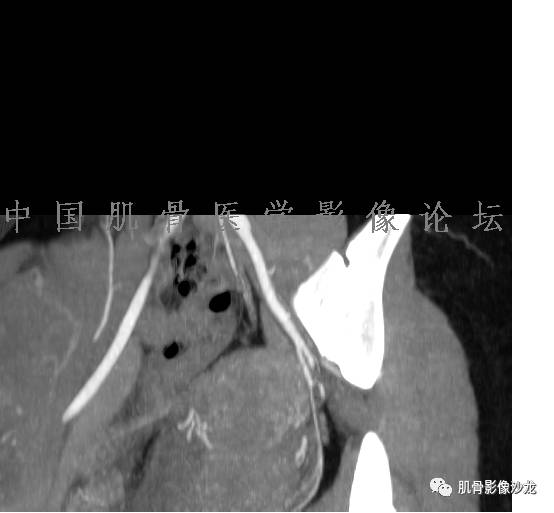

患者于2月前无明显诱因下出现腰骶部疼痛,夜间为重,逐渐加重伴左下肢麻木、疼痛,并有行走活动受限,在我院就诊,摄腰椎及骶髂部CT提示:腰椎骨质退变,腰3-4、4-5椎间盘膨出,骶髂关节炎。自用非甾体抗炎药无好转,再次来院就诊,门诊拟“骶髂关节炎”收住我科。病程无间歇性跛行,大小便正常。

辅助检查:腰椎及骶髂部CT提示:腰椎骨质退变,腰3-4、4-5椎间盘膨出,骶髂关节炎。

雪舞 :第二例,位于骶骨,有骨质破坏并有软组织肿块,软组织肿块边界清

雪舞 :第二例挺难的,骨质破坏是溶骨性的,局部皮质中断,软组织肿块外缘光滑

雪舞 : 软骨肉瘤的发病率居原发性恶性骨肿瘤的第三位,其特点是肿瘤内具有软骨基质

雪舞:弓形钙化,钙化比例少于面积的1/3,钙化边缘模糊

雪舞 : 都是软骨肉瘤鉴别于内生软骨瘤有意义的区别点